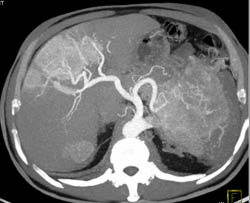

Islet Cell Tumor With Liver Metastases